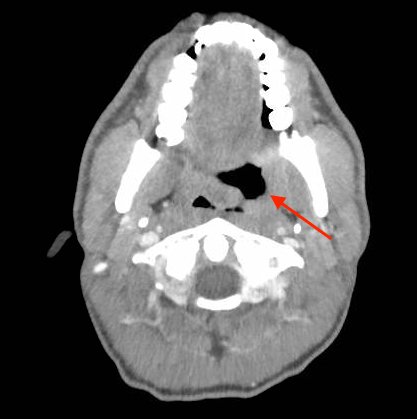

The photograph demonstrates an area of ulcerative tissue at the left palatine tonsil without surrounding erythema or purulent drainage. The computed tomography (CT) scan shows a large ulceration of the left soft palate and palatine tonsil (red arrow). There is no evidence of skull base osteomyelitis. There is suppurative lymphadenopathy with partial left jugular vein compression due to mass effect (yellow highlight). There is mild nasopharyngeal airway narrowing with architectural distortion (blue arrow), but no other evidence of airway obstruction.